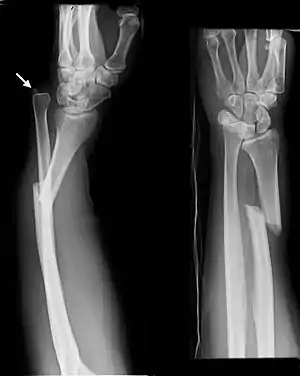

| Galeazzi fracture. Arrow points at the dislocated ulnar head |

شکستگی گالیوزی - (به انگلیسی: Galeazzi fracture) شکستگی دیاستال سوم زند بالایی با جابجایی مفصل رباط دیستال میباشد. یک شکستگی متداول شامل شکستگی و جدا شدن از ناحیه اتصال دومی سوم و سومین شعاع همراه با سوزش یا جابجایی مفصل رشته متصل به رادیولننال میباشد. آسیب در محل مفصل ساعد میباشد.[1]

تورم بافت و بافت نرم در محل شکستگی زند بالایی و در مفصل مچ دست وجود دارد. این آسیب با ارزیابی رادیوگرافی تأیید میشود. ترومای ساعد ممکن است با سندرم کمپارتمان مرتبط باشد. آسیب در عصب بین استخوانی قدامی (AIN) نیز ممکن است وجود داشته باشد، که ممکن است نادیده گرفته شود، زیرا هیچ روش خاصی برای تشخیص آن وجود ندارد. عصب اصلی، AIN عصب بخش حرکتی است. جراحت به AIN میتواند موجب فلج شدن ماهیچه دراز خمکننده شست دست و ماهیچه عمقی خمکننده انگشتان دست و عضلات انگشت اشاره شود و منجر به از دست دادن مکانیزم حرکت بین انگشت شست و انگشت اشاره شود. شکستگی گالیوزی گاهی اوقات در مچ دست موجب آسیب به عصب رادیال، تاندونهای انقباضی یا عضلات میشود.